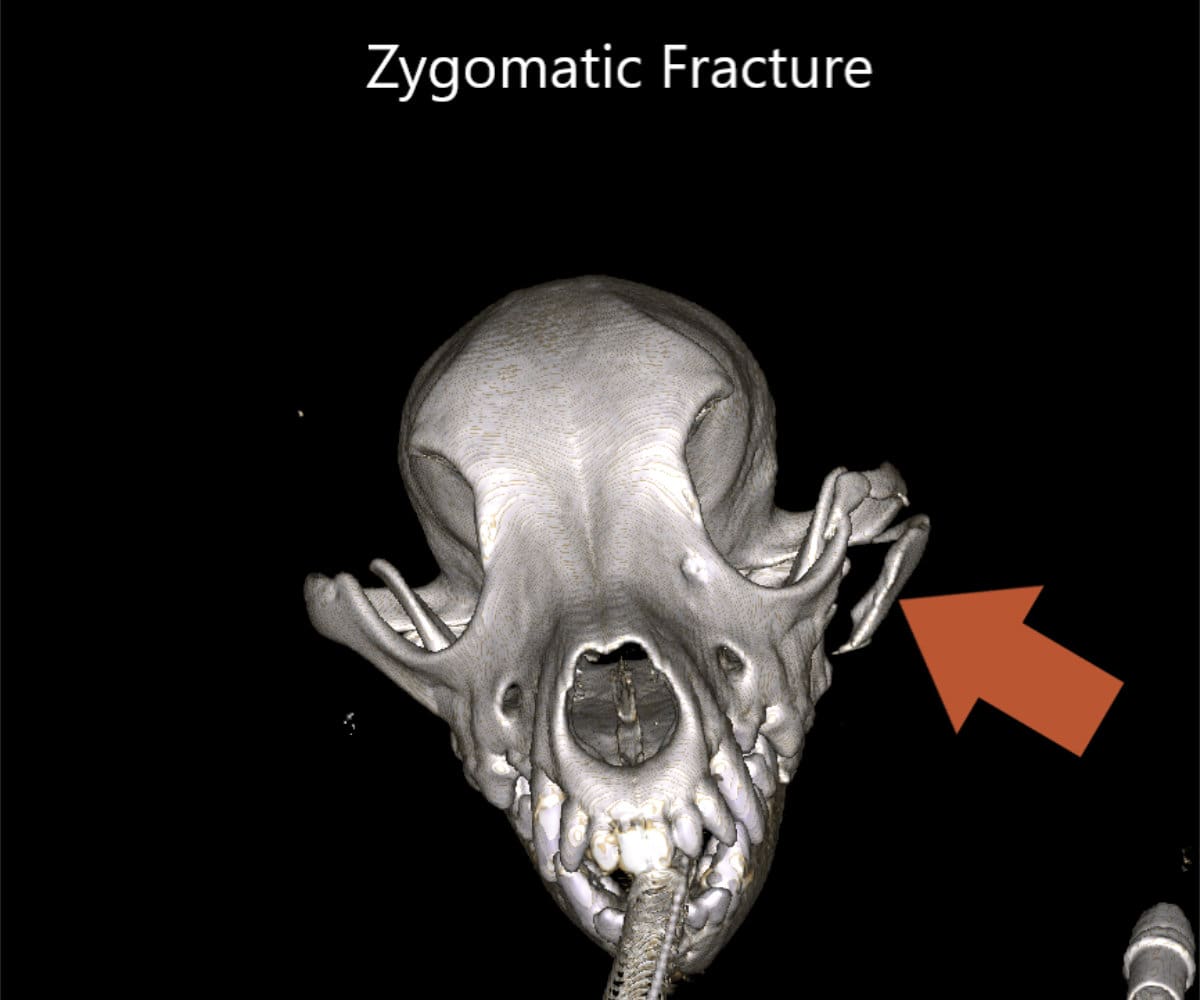

The advantages extend beyond diagnosis, as CBCT enables intricate 3D reconstructions of the skull, providing invaluable support to our doctors in the meticulous planning process for facial plating procedures.

Our CBCT VetCAT unit is easily rolled up to our treatment table and takes only 40 seconds to complete a scan. It has proven to be invaluable in the diagnosis and treatment planning for pets with periodontal, endodontic and cancerous disease conditions. It is also indispensable in the evaluating our trauma cases with jaw fractures.